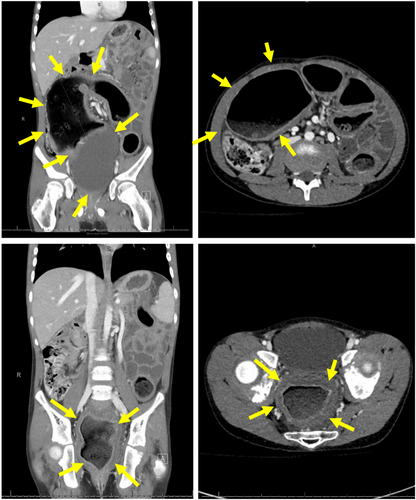

⚠️ Food impaction + normal-ish biopsy ≠ no #EoE.

Mahon et al. show 4 kids with sub-diagnostic eosinophil counts at #EFI who ALL had EoE confirmed on repeat scope. Don't let them fall through the cracks! 👇 #PedsGI #Esophagus #GITwitter